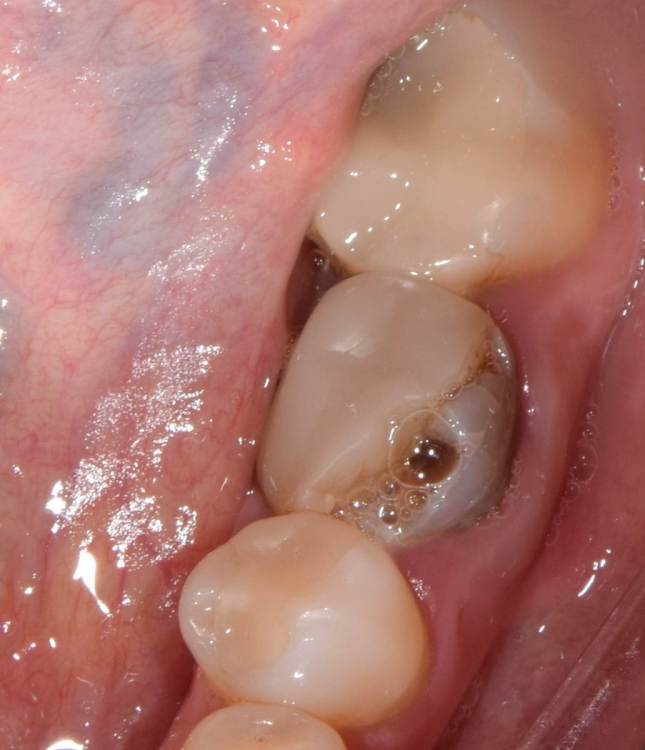

Dr.Deletle Опубликовано 22 июля, 2023 Поделиться Опубликовано 22 июля, 2023 (изменено) Этот кейс интересен тем, что у пересаживаемого 2.8 полностью сформированы корни. Пациент Н., 35лет, зуб 3.6 подлежит удалению по терапевтическим показаниям. Донором был выбран зуб 2.8. Фото №1, 2 - ситуация ДО на фото и срезе КЛКТ Фото №3 - планирование на реконструкции ОПТГ из КЛКТ Фото №4 - шаблон зуба 2.8 Фото №5, 6 - операция, удален 3.6, припасован шаблон, пересажен 2.8 (фиксирован швами и шиной к 3.7) Фото №7 - КТ сразу после пересадки Фото №8, 9 - депульпирование пересаженного 2.8 через 2 недели Фото №10 - снятие шины через 2нед после пересадки Фото № 11, 12, 13 - состояние в полости рта и на срезе КТ через год после пересадки, видно сформированное периодонтальное пространство, здоровая костная ткань, жалоб у пациента нет, полноценно жует как обычным зубом Изменено 22 июля, 2023 пользователем Dr.Deletle 4 3 Ссылка на комментарий